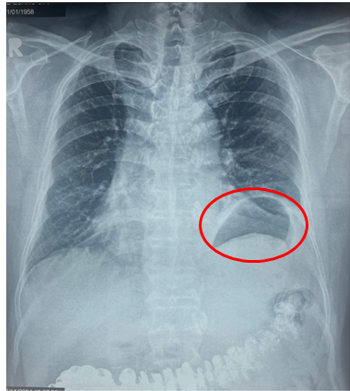

| Hình ảnh vòm hoành trái cao bất thường do nhão cơ hoành trái làm giảm thể tích lồng ngực trái gây khó thở gắng sức cho bệnh nhân - Ảnh: BVCC |

Tại Bệnh viện Bình Dân, sau khi thăm khám lâm sàng và xem kết quả chụp X-quang ngực và MSCT-scan ngực, các bác sĩ chẩn đoán ông bị nhão hoành trái với hình ảnh vòm hoành trái nhô cao bất thường. Tình trạng này làm giảm thể tích lồng ngực trái, đây chính là nguyên nhân khiến ông bị khó thở khi gắng sức nhiều tháng nay mà ông không rõ nguyên nhân.